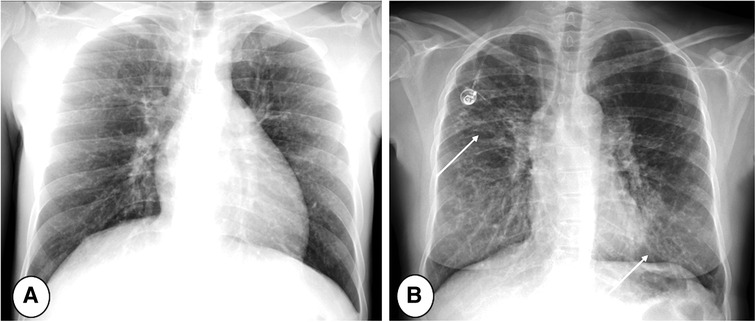

FIGURE 4

www.frontiersin.org

Figure 4. End-inspiratory CT of a cystic fibrosis patient (A) without and (B) with respiratory tract exacerbation, lung window. Note bronchiectasis and mucus plugs, especially in the middle lobe and lingula (thin arrows). The only difference indicating RTE is an increase in central mucus plugs (thick arrow).

FIGURE 5

Figure 5. Axial CT of 5 months old patients with CF, thickness 0.7 mm, scanned in single source-mode with pitch 1.2 (A) and repeated in double source-mode with pitch 3.2 (B). Note that respiratory artifacts are absent using an higher pitch acquisition (B), providing a high image quality and facilitating the detection of atelectasis in the left lower lobe (arrows).